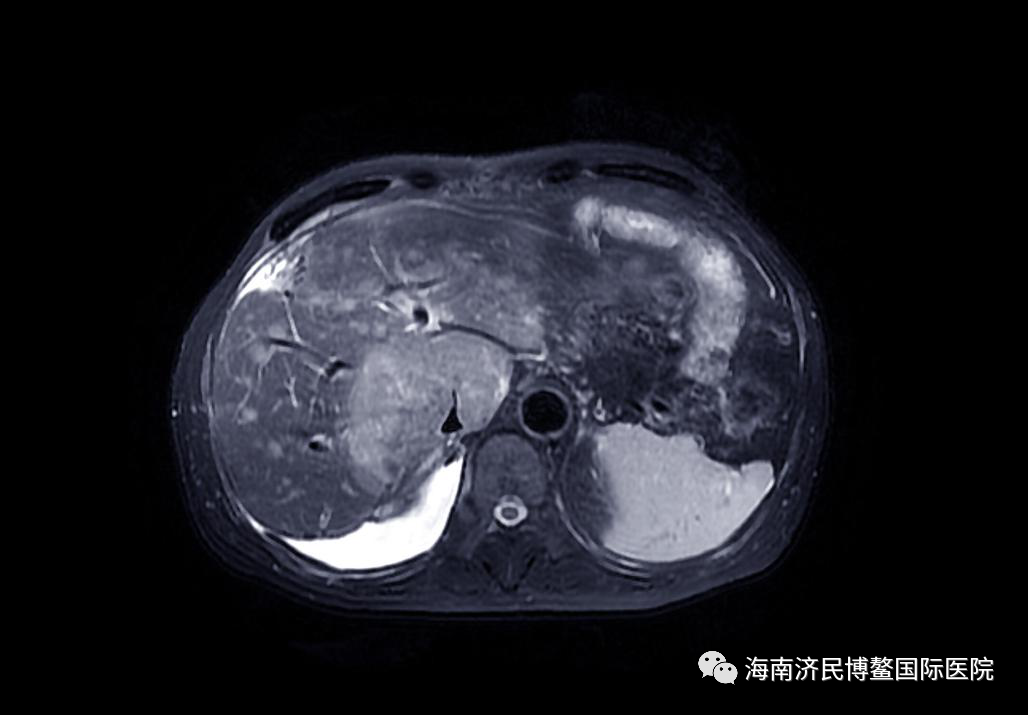

治疗后:6月28日最大肿瘤病灶体积54mm*26mm*64mm